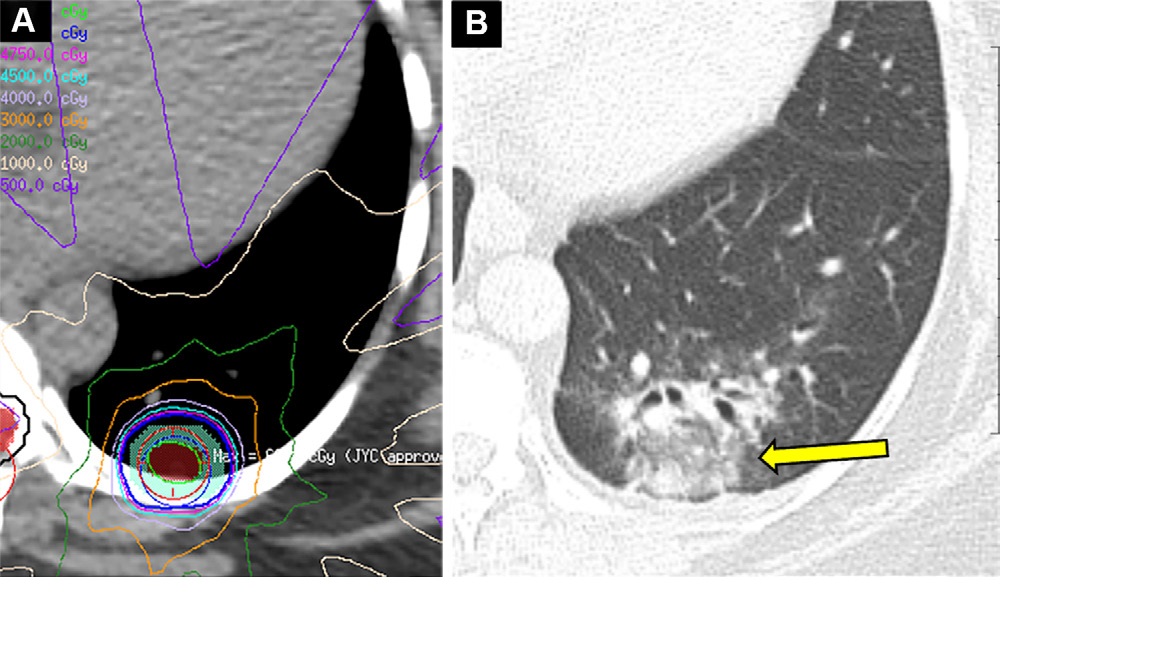

- Overuse of pulmonary CT angiography (CTA) compared with D-dimer testing for suspected pulmonary embolism. A research group found that pulmonary CTA was performed as the initial test in 60.8% of patients with low pretest probability of stroke, while D-dimer testing was underutilized, leading to treatment delays, higher costs, and patient exposure to radiation.

- Overuse of CT in patients with respiratory symptoms. Researchers noted that the use of CT in the emergency department quadrupled from 2.2% to 9.4% from 2001-2002 to 2009-2010. The largest increase was among patients with nonacute upper respiratory tract symptoms. At the same time, there was no change in antibiotic prescriptions and hospital admission over the time periods, indicating that rising CT use led to no change in patient management.